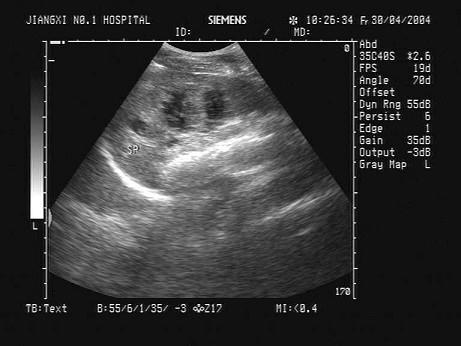

问题 某患者摔伤左腹部,左腹部疼痛不适,恶心,无呕吐。急诊超声检查,根据左腹部超声声像图,诊断为?(?)

选项 A.正常声像图 B.脾破裂 C.脾淋巴管囊肿 D.脾梗死 E.脾结核

答案 B